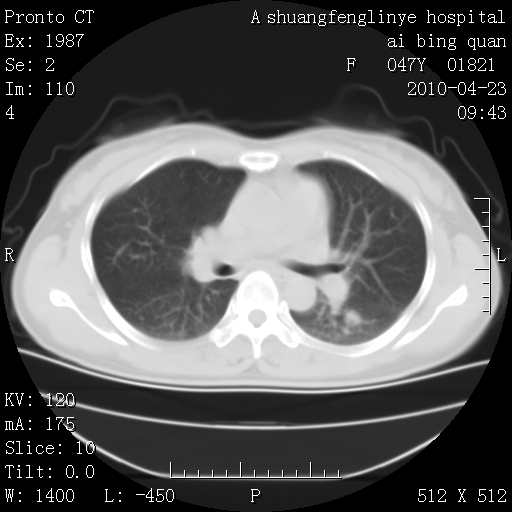

标题: CT25944:胸痛、气短、前几日高烧!肺Ca?请会诊! [打印本页]

标题: CT25944:胸痛、气短、前几日高烧!肺Ca?请会诊!

kaolv 周围型肺癌并同肺转移

双肺多发结节,考虑转移瘤,肺癌肺转移不除外

周围型肺癌并肺转移

双肺多发结节,部分密度较高,最大结节边缘光滑。临床有“胸痛、气短、前几日高烧”病史。首选考虑:右肺感染性病变!建议积极消炎后复查!